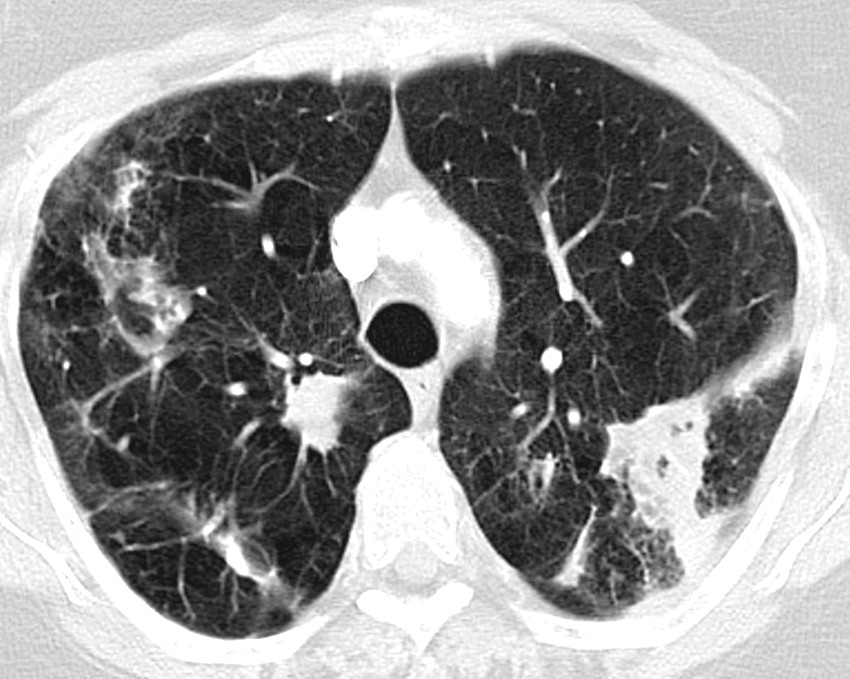

Radiological examination

When NTM pulmonary disease is suspected, the patient should undergo a CT thorax. The two most common radiological presentations are the fibrocavitary and nodular bronchiectasis forms (23, 24). The fibrocavitary form has cavitary lesions, most frequently in the upper lobes, with radiological findings that resemble tuberculosis (Fig. 1). This form often has a more aggressive course, and is seen most frequently in elderly men who smoke or have another pulmonary disease, such as chronic obstructive pulmonary disease, or have had tuberculosis. The nodular bronchiectasis form is characterised by multifocal bronchiectasis and small nodules, most frequently in non-smoking, elderly women. This form is also over-represented in patients with a low body mass index, scoliosis, pectus excavatum, mitral prolapse, and in tall persons (17, 19).